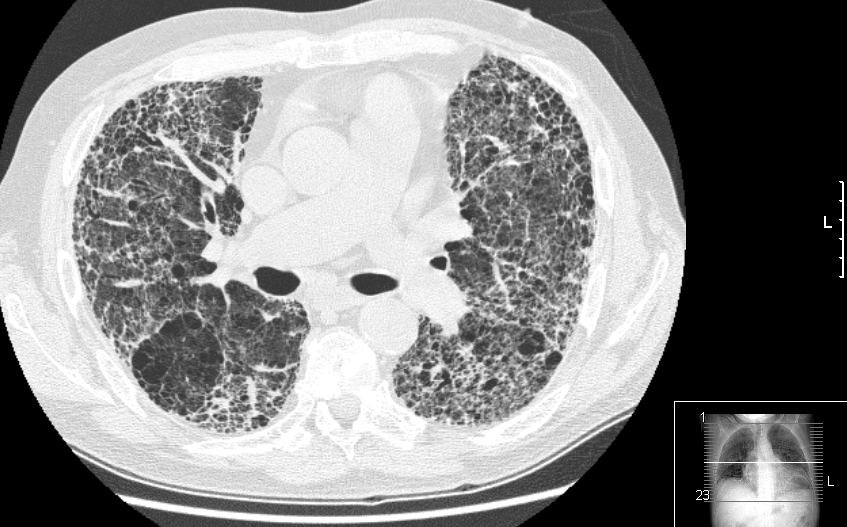

Eficacia de los antibióticos preventivos en la fibrosis pulmonar idiopática

En pacientes con formas moderadas a graves de la enfermedad, el tratamiento con cotrimoxazol oral no redujo un resultado combinado de mortalidad, trasplante u hospitalización no selectiva en comparación con placebo. JAMA, 8 de diciembre de 2020.